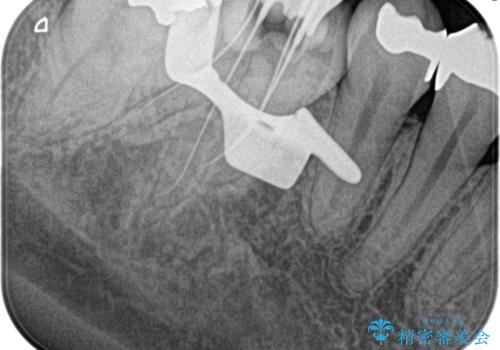

【根管治療】昨日から眠れないぐらい歯が痛い

- 昨日から夜も眠れないぐらい痛いことを主訴に来院されました。

検査の結果、不可逆性歯髄炎の診断とし根管治療を行なっております。

- 精密根管治療(イニシャルケース,大臼歯):122,000円、ファイバーコア:22,000円費用は治療当時の料金となります